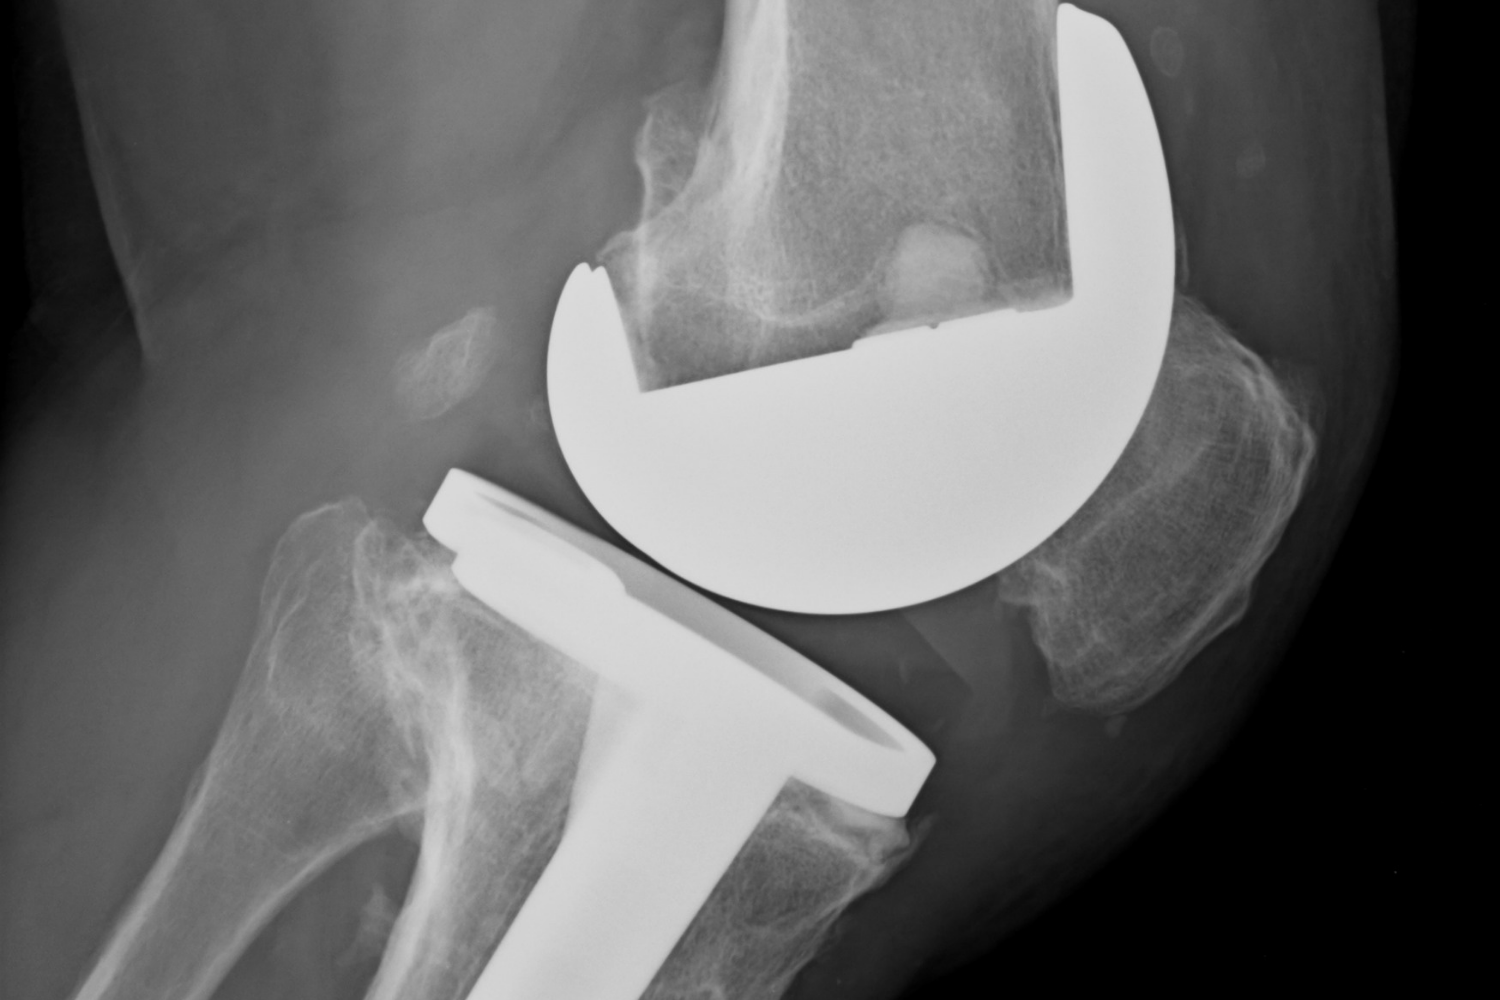

Prótesis articulares

Prótesis articulares (cadera, rodilla)

Reemplazo de la articulación desgastada o dañada por componentes artificiales de alta duración.

Reemplazo Articular de Rodilla en Lima

Prótesis de Rodilla

Olvídate del dolor con una prótesis de rodilla. Nuestro equipo te brindará una solución personalizada para que puedas volver a disfrutar de tus actividades favoritas.

Recupera la movilidad y olvida el dolor de la artrosis avanzada con el reemplazo articular total.